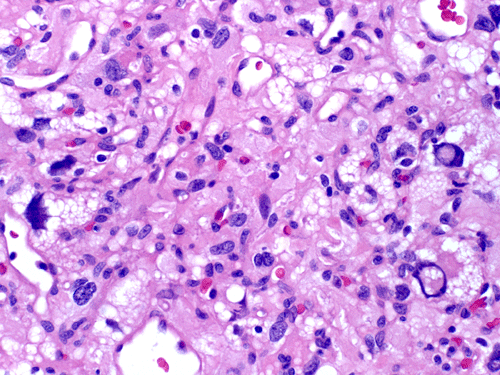

The mass consists of a mixture of spindle cells and clear cells. There is a rich vascular network (Panel A) with sinsusoidal dilatation but no anastomosis of the vascular channels. The endothelial cells appear lean and not protruding into the vascular channel. The clear cells appear to have foamy cytoplasm (̃ in Panel B). The nuclei are hyperchromatic and may appear slighly grooved or lobuated. On immunohistochemistry, the foamy cells are strongly reactive for inhibin (Panel C). These cells are also reactive for S100 protein (Panel D)  and neural specific enolase (Panel E) . No immunoreactivity for epithelial membrane antigen (EMA) is observed (Panel F). The tumor is not immunoreactive for cytokeratin.

More thant two-third of hemangiomas occur as mural nodules associated with fluid-filled cysts in the cerebellum.  The cyst wall itself is composed of benign neuronal glial cells.  The specimen appears reddish-brown to yellow, due to their dense vasculature and high lipid content.  Fresh tissue often gives a liver like consistency and color. The fluid within the cyst is xanthochromatic and rarely hemorrhagic.  Less common gross appearances include solid and microcystic forms.

Microscopically, hemangioblastomas consist of foamy to clear stromal cells interspersed with endothelium lined vascular channels.  Clear vacuoles within the stromal cells can be stained with Oil red-O or similar stain if applied to frozen sections.  The stromal cells stain strongly for epidermal growth factor receptor (EGFR) and platelet-derived growth receptor factor alpha (PDGF-alpha) 12 and inhibin 13. The stromal cells are typically negative for epithelial membrane antigen (EMA) and cytokeratin 14.  In a small number of cases, the stromal cells express glial fibrillary acidic protein (GFAP)  7, 14 and S100 protein 14. These staining results should be interpreted with case as they may represent entrapped glial cells. The admixed capillaries will stain for with typical endothelial markers (Factor-VIII and others) 15, but the stromal cells are typically negative for the endothelial markers. To this date, the pathogenesis and cell origin of hemangioblastomas is not certain.